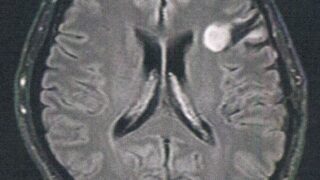

GLIOMA:手術後126ヶ月目の検査

手術から10.5年が経過した。半年ごとの定期検査です。検査概要びまん性星細胞腫グレード2(悪性転化しやすい腫瘍)MRI検査: 造影剤なし / 造影剤あり造影剤ありの場合:4時間前から絶食し、MRIの1時間前に血液検査を済ませる。診断結果MR...